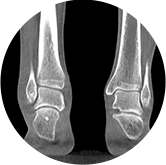

足踝

精准诊断

手术方案规划

术后随访